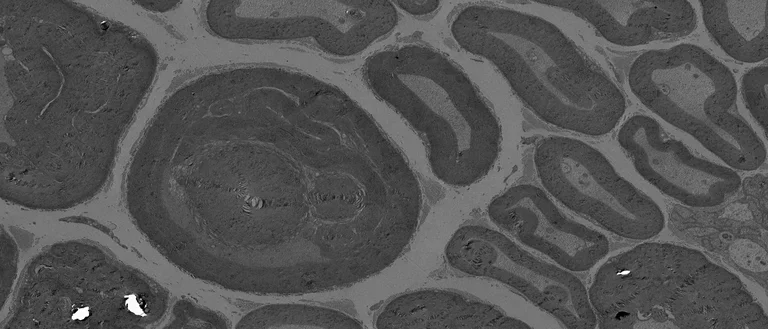

The peripheral nervous system possesses an astonishing capability for self-repair, however it can eventually become overwhelmed by injury or disease resulting in impaired motor and sensory function. The compilation of genetic disorders, metabolic diseases, environmental stressors, and injury that lead to sensorimotor dysfunction, termed peripheral neuropathies, make this class of disease a common neurological disorder. Historically, nervous system injuries and diseases are studied from a ‘neuron-centric’ perspective, however peripheral nerve regeneration also depends on axon-to-glia signaling to induce Schwann cells plasticity. Schwann cells respond to axonal damage by transiently transdifferentiating into specialized ‘repair cells’ that facilitate axonal regrowth and reinnervation of axonal targets, promoting a return to normal sensorimotor function.

Research in my lab lies at the intersection of the fields of glial biology, axonal regeneration and cytoplasmic-to-nuclear signaling. We are focused on understanding the molecular mechanisms of nervous system plasticity to gain insight into regeneration after injury and during chronic disease. The long-term goal of the lab is to harness how Schwann cells maintain and induce their regenerative capacity to inform future therapeutics.